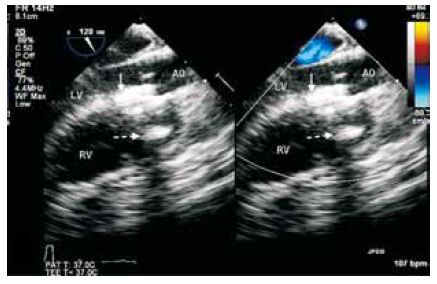

臨床資料?患兒,男,3歲。因“體檢發現心臟雜音1+年”入院。入院查體可于胸骨左緣第2至第3肋間聞及全收縮期III/6級雜音。入院后心臟彩色超聲心動圖提示“先天性心臟病:室間隔缺損(干下型)”,彩色超聲心動圖檢查未發現明顯主動脈瓣脫垂或反流,患兒其他術前檢查均無特殊。結合我院長期應用胸骨旁小切口經心室穿刺封堵室間隔缺損的經驗[1-2],為取得更好的微創治療效果,故采用經皮穿刺右心室封堵的方法完成該病例的治療。患兒術前經胸超聲心動圖檢查需明確右心室流出道有無明顯冠狀動脈分支分布,全身麻醉后再次行食管超聲檢查確認診斷并測量室間隔缺損大小。我們選取胸骨左緣第3肋間,穿刺前外科醫生以手指按壓肋間隙擬穿刺部位并結合食管超聲圖像明確穿刺點。為避免損傷乳內動脈,穿刺點貼近胸骨邊緣。取20 G鞘管穿刺針穿刺皮膚,在食管超聲連續引導下穿刺進入肺動脈瓣下右心室流出道,拔出針芯交換引導鋼絲進入右心室并通過室間隔缺損進入左心室。取出穿刺針鞘管,經鋼絲引導經皮穿刺置入6F輸送鞘并按照以往報道的經心室穿刺干下型室間隔缺損封堵技術完成室間隔缺損封堵[1]。食管超聲確認封堵無殘余分流及主動脈瓣反流等問題后,釋放封堵器。與以往技術不同之處在于,封堵器釋放后并不立即撤出穿刺輸送鞘管,需保持鞘管尖端位于右心室流出道內(圖 1),并再次通過輸送鞘管置入一枚5 mm膜周部室間隔缺損封堵器(上海形狀記憶合金有限公司)。該封堵器左傘盤先于右心室流出道內釋放(圖 2),并回拉使其緊貼右心室流出道穿刺處內壁(圖 3),接著于心臟外釋放右傘盤,完成對穿刺點的封堵(圖 4)。確認該創道封堵器兩傘盤位置后完成釋放,取出鋼纜,經鞘管注入液體明膠(Surgiflo,美國)填充心臟外右傘盤,并一邊緩緩取出鞘管一邊注入液體明膠填充皮下及胸壁創道。封堵結束后胸壁僅見一針道創口,無需縫合(圖 5)。患兒術后恢復良好,圍術期及1年隨訪期內均未發現心包積液、殘余分流、主動脈瓣反流、右室流出道梗阻或心律失常。

討論?干下型室間隔缺損因其與主動脈瓣關系密切,易繼發主動脈瓣脫垂及反流而需要早期處理[3]。傳統開胸體外循環手術創傷大,而射線下經皮穿刺介入導管封堵又因技術難度極大而一般被認為不適用于干下型室間隔缺損。過去數年間,本中心利用劍突下或胸骨旁小切口經心室穿刺封堵該類缺損已經取得了較好的療效,將干下型室間隔缺損的微創治療帶入了V 2.0時代,但2 cm左右的手術切口仍有改進的空間。受近年來再次手術患者經皮穿刺左心室心尖技術的啟發[4],我們創新性得將以上兩種技術結合起來,于2015年初在國際范圍內首次完成了非再次手術的干下型室間隔缺損經皮穿刺右心室治療并取得成功,隨訪1年效果滿意。在右心室流出道無明顯冠狀動脈分布的情況下,連續食管超聲檢查可以很好地分辨穿刺路徑與相關解剖結構的關系,安全引導經皮右心室穿刺。封堵完成后,選擇使用封堵器完成右心室創道關閉具有可行性,在熟練操作的情況下安全可靠,本例未見封堵器移位、心包積液或心臟壓塞等明顯并發癥發生。